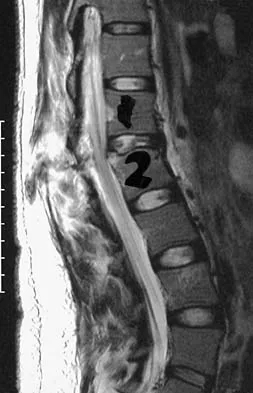

Question 58 High Yield

Figure 33 shows the MRI scan of a 55-year-old woman who has had a 6-week history of back and leg pain. Which of the following clinical scenarios is most consistent with the MRI scan findings at L4-L5?

Detailed Explanation

The MRI scan reveals a L4-L5 foraminal disk herniation originating from the L4-5 disk space that has migrated up into the foramen, compressing the left L4 nerve root. There is normal distribution of the roots in the cerebrospinal fluid, excluding arachnoiditis as a diagnosis, and disk herniation in this location would not result in cauda equina syndrome or myelopathy.